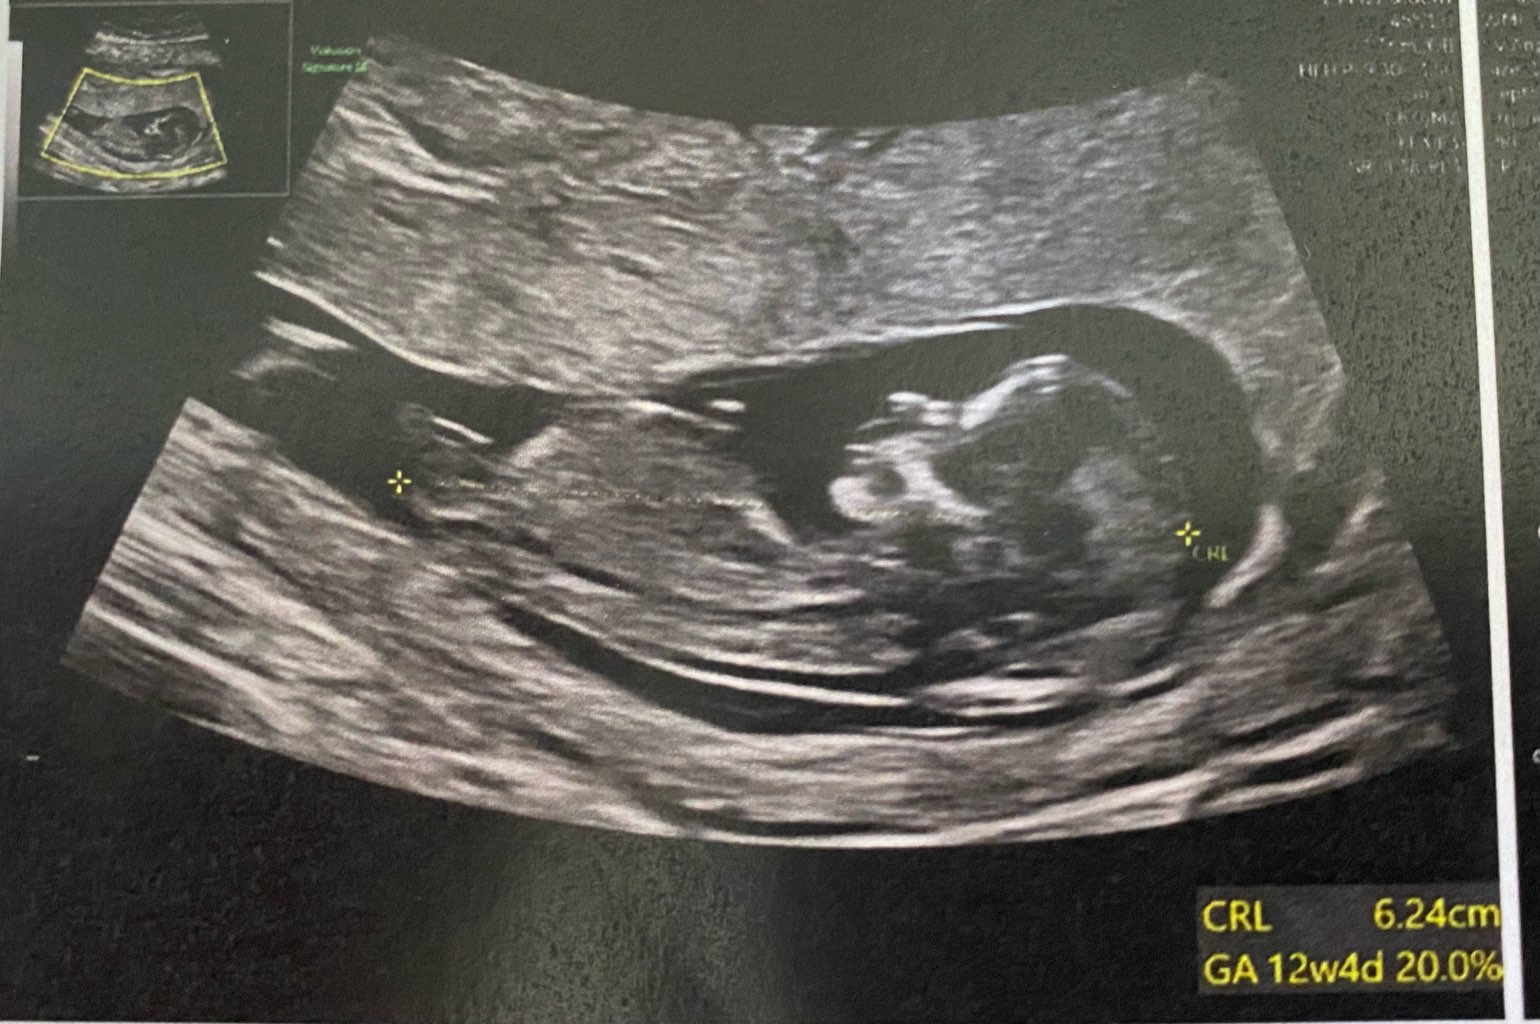

Jednak synuś![]()

Dziewczynka?A kogo tu obstawiacie?

nie chciał mówić, mówił tylko że łechtaczka przypomina penisa więc łatwo się pomylić w płciDziewczynka?Czy lekarz cos zasugerował podczas robienia usg?

Hmm.. to chyba bedziesz musiała poczekać, tak jak janie chciał mówić, mówił tylko że łechtaczka przypomina penisa więc łatwo się pomylić w płci![]()

Tylko że w 12 tygodniu nie ma ani łechtaczki ani penisa, wszystkie dzieci mają wyrostek płciowynie chciał mówić, mówił tylko że łechtaczka przypomina penisa więc łatwo się pomylić w płci![]()

mówię co lekarz powiedział wczoraj (14+0) a zdjęcie jest z prenatalnych. A masz podejrzenia?Tylko że w 12 tygodniu nie ma ani łechtaczki ani penisa, wszystkie dzieci mają wyrostek płciowy![]()